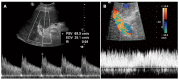

Orthotopic liver transplantation (OLT) represents a major treatment for end-stage chronic liver disease, as well as selected cases of hepatocellular carcinoma and acute liver failure. The ever-increasing development of imaging modalities significantly contributed, over the last decades, to the management of recipients both in the pre-operative and post-operative period, thus impacting on graft and patients survival. When properly used, imaging modalities such as ultrasound, multidetector computed tomography, magnetic resonance imaging (MRI) and procedures of direct cholangiography are capable to provide rapid and reliable recognition and treatment of vascular and biliary complications occurring after OLT. Less defined is the role for imaging in assessing primary graft dysfunction (including rejection) or chronic allograft disease after OLT, e.g., hepatitis C virus (HCV) recurrence. This paper: (1) describes specific characteristic of the above imaging modalities and the rationale for their use in clinical practice; (2) illustrates main imaging findings related to post-OLT complications in adult patients; and (3) reviews future perspectives emerging in the surveillance of recipients with HCV recurrence, with special emphasis on MRI.